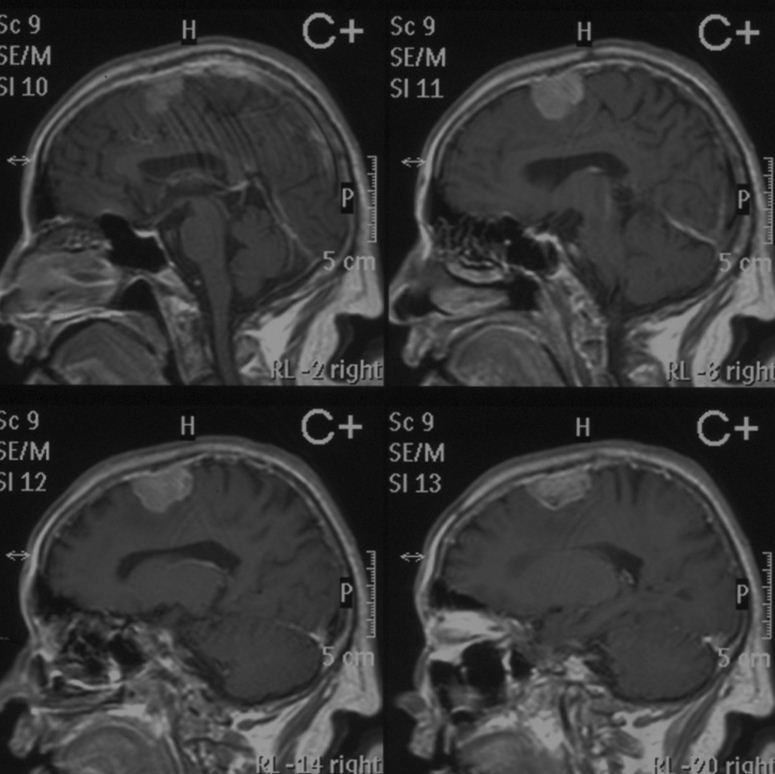

数字神经外科技术辅助平舆县人民医院完成脑膜瘤切除术

颅骨良性肿瘤的影像诊断

良性脑肿瘤不开刀可以吗脑膜瘤4年未治疗病例

头骨,脑,3d扫描,脑肿瘤,磁共振成象扫描

【读片】老年人的颅骨 [病例帖]